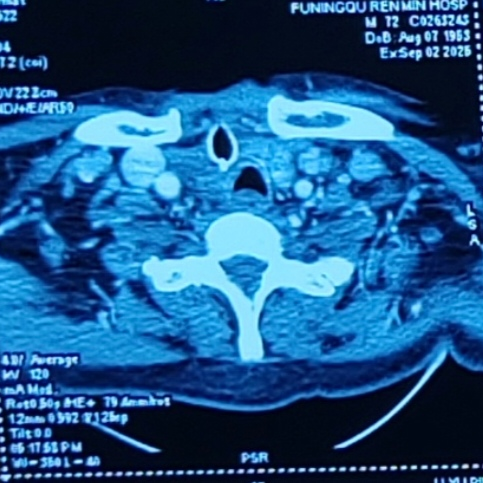

治疗前

治疗后

经过两个月的规范治疗,9月5日患者复查时,影像学检查显示肿瘤体明显,电子鼻咽喉镜证实气道通畅,赵龙珠主任团队为其拔除气管套管并封闭造瘘口,患者恢复自主呼吸。

术后病理显示为BRAF V600E突变型ATC,PD-L1高表达(CPS评分≥90),为甲状腺未分化癌。基于基因检测结果,赵龙珠主任团队联合肿瘤科专家制定个性化治疗方案:采用达拉非尼联合曲美替尼靶向治疗,同时联合免疫治疗,这种治疗策略同时针对了肿瘤生长的驱动基因和患者自身的免疫系统,实现了双重打击。